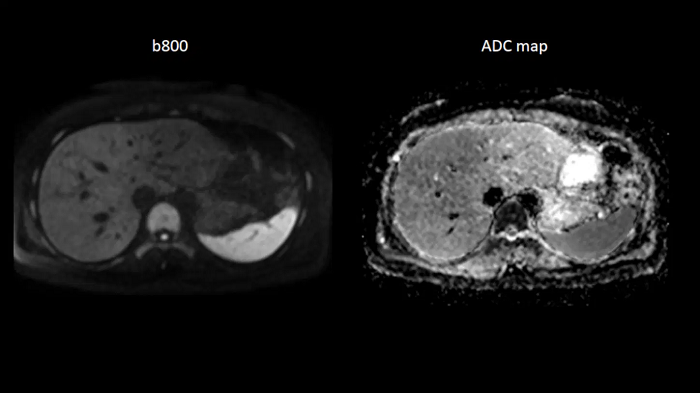

Body diffusion imaging

For all-inclusive abdominal MR capabilities, outstanding quality diffusion imaging.

MAC-ID: 7aaaa0165.

MAC-ID: 7aaaa0165. Image Credit: Siemens Healthineers